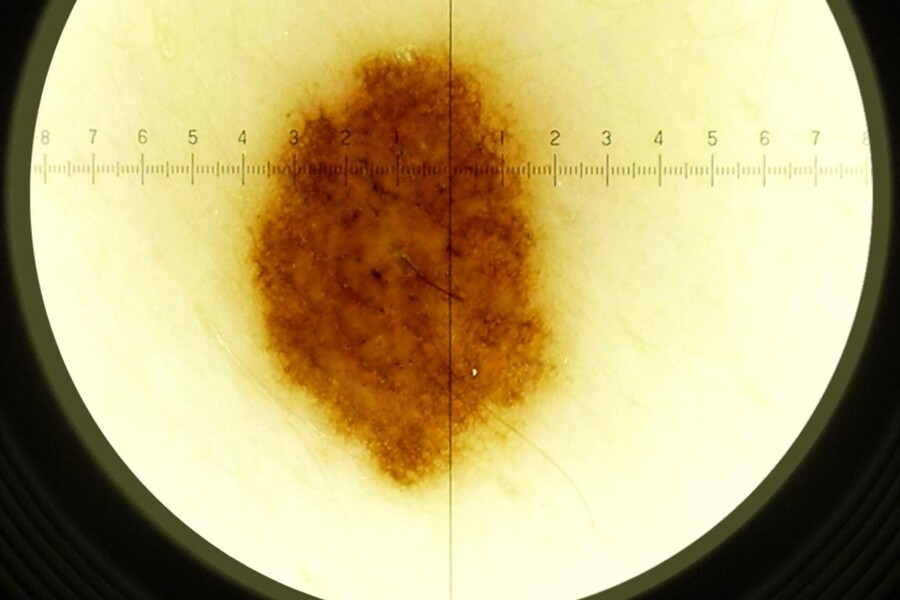

Běžný pigmentový névus má pestrý vzhled. Může být plochý nebo vyvýšený, od několika milimetrů až po rozsáhlé plochy. Téměř vždy je hnědé barvy, mohou se však lišit odstínem. Základem však je, že barva je v celém útvaru stejná. Tím se liší od névů atypických neboli dysplastických. Tyto névy se objevují především u dospělých osob, které mají na těle větší počet znamének a objevují se zejména v horní části trupu. Névy jsou různě velké, nepravidelně tvarované, nestejnoměrného zabarvení od růžové, přes světle, tmavě hnědou až černou. Typické pro dysplastický névus je tmavý střed a světlejší okraje. Někdy je obtížné odlišit tento névus od rakoviny kůže, agresivního nádoru kůže - melanomu. To je možné jen odebráním vzorku na histologické vyšetření.

Některé névy se mohou zvrhnout v rakovinu kůže. Platí to hlavně o dysplastických névech. Proto je potřeba pravidelného sledování těchto znamének. Rovněž v případě jakýchkoliv pochybností je na místě návštěva kožního lékaře. Podezřelá jsou znaménka, která mají nepravidelný tvar, jsou neostře ohraničená, větší než půl centimetru nebo se rychle zvětšují, dále znaménka černá nebo vícebarevná a hrbolatá. Takto změněná znaménka je nutno chirurgicky odstranit. Pokud se rakovina kůže neodhalí včas, končí smrtí. Proto nepodceňujte návštěvu ordinace kožního lékaře, v rámci prevence by ji měl člověk absolvovat jednou do roka, ideálně po letní sezóně.